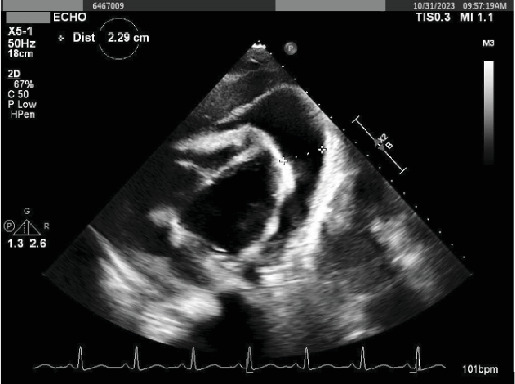

原发性纵隔大b细胞淋巴瘤(PMBCL)是一种高度侵袭性的恶性肿瘤,主要见于30岁左右的女性患者。这种罕见疾病的发病率为百万分之0.4,传统上表现为B型症状或压迫性后遗症,如SVC综合征或呼吸窘迫。在本报告中,我们报告了一位年轻女性的病例,她表现为心悸和心动过速,没有心肺按压症状,诊断为位于左心室的16厘米浸润性PMBCL。

Primary mediastinal large B-cell lymphoma (PMBCL) is a highly aggressive malignancy primarily observed in female patients during their third decade of life. This rare condition, with an incidence of 0.4 per million, traditionally presents with B symptoms or compressive-based sequela such as SVC syndrome or respiratory distress. In this report, we present the case of a young female who presented for palpitations and tachycardia without cardiopulmonary compressive-based symptoms diagnosed with a large 16-cm infiltrative PMBCL localized in the left ventricle.